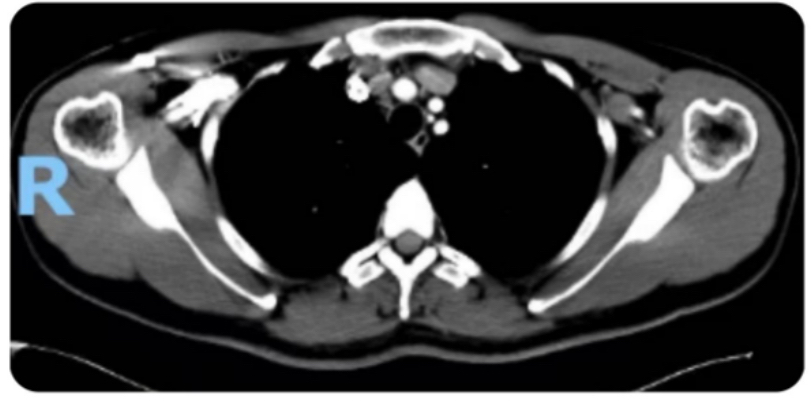

据悉,患者为36岁青年男性,术前甲状腺彩超提示:甲状腺右叶结节为2.2x1.5x1.2cm(TI-RADS 5类),增强CT提示:右侧颈部、气管前方、纵隔内多发肿大淋巴结,FNA示:(右叶)甲状腺髓样癌,(气管周围淋巴结)查见癌细胞,(右颈部淋巴结)查见癌细胞。在传统治疗方案中,上纵隔淋巴结清扫多需联合开胸或胸腔镜手术,不仅手术创伤大、术后恢复时间长,还可能引发肺部感染、胸廓畸形等并发症,给患者带来额外负担。面对这一治疗难题,盛蕾副主任医师充分评估患者病情,与曾庆东教授、吕斌教授反复研讨手术方案后,决定突破传统入路限制,创新性采用经颈部切口入路腔镜辅助上纵隔淋巴结清扫术。

术中探查见患者甲状腺右侧II,III,IV区及上纵隔淋巴结肿大,部分融合成团,大者约3cm,自颈内静脉向外侧剥离淋巴结,于锁骨上方水平向深面切开脂肪组织至前、中、后斜角肌及肩胛提肌表面,并沿上述肌肉表面向上游离,于二腹肌后腹下方行腔镜辅助右颈部功能性淋巴结清扫,术中显露并保护舌下神经、膈神经、臂丛神经、颈横血、副神经。继续行上纵隔淋巴结清扫术,钝性游离胸腺,显露无名动脉。打开血管鞘膜,腔镜下分离无名动脉下方、右侧无名静脉与主动脉弓上方的2R区淋巴结,将肿大淋巴结完整切除,术中注意保护迷走神经、喉返神经、淋巴管、右胸膜及主动脉弓等重要脏器。